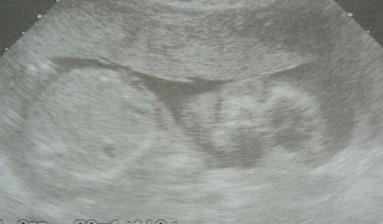

Micinek

Tak není to tak dávno co jsme vytvářeli album na bereme se a už šup těsně na měsíc od mých 3Otin jsme štastni ještě víc, budeme mit mimi a strašně se těšíme o to víc, že to nebylo plánované a vyšlo to na 1! Je to sice místo svatební cesty, která se díky Tomitouru nekonala, ale stojí to za to!